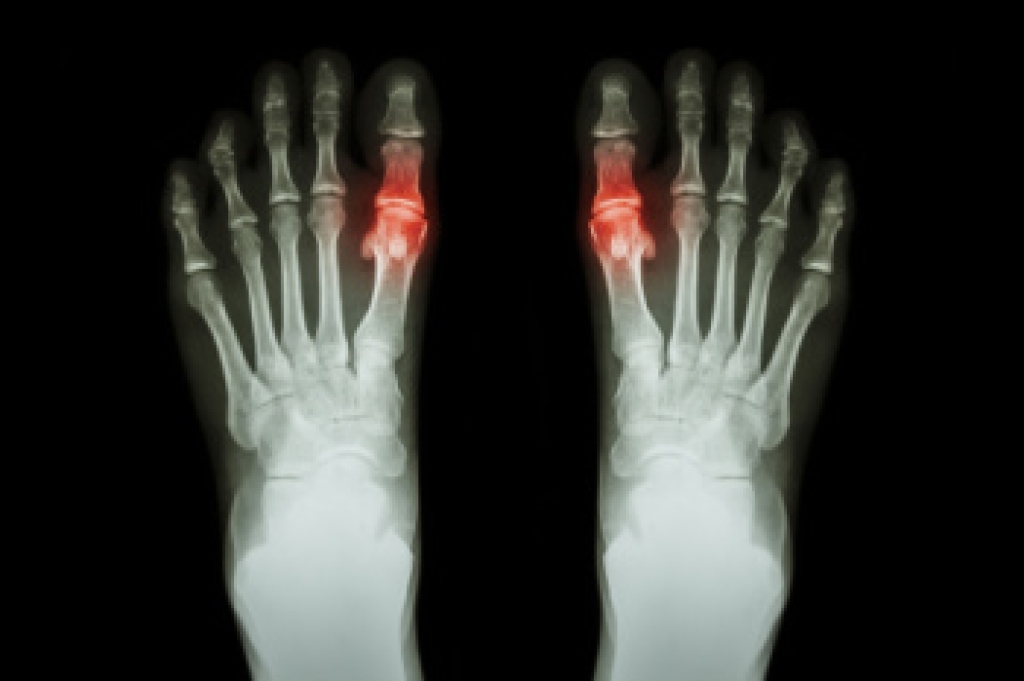

Gout, a form of inflammatory arthritis, is often triggered by certain foods high in purines, which are natural compounds found in various food sources. Purines break down into uric acid in the body. When uric acid levels become elevated, it can lead to the formation of urate crystals in the joints, like the big toe, and cause gout flare-ups. Foods rich in purines include red meat, organ meats like liver and kidneys, shellfish, and certain types of fish like anchovies and sardines. Additionally, alcohol, particularly beer and liquor, can increase uric acid levels and trigger gout attacks. Sugary beverages and foods high in fructose can also contribute to gout symptoms. Limiting consumption of these purine-rich foods and beverages, and focusing on a balanced diet that includes plenty of fruits, vegetables, whole grains, and low-fat dairy products, can help manage gout symptoms and reduce the frequency of flare-ups. If you have gout attacks in your big toe, it is suggested that you consult a podiatrist who can help you to manage this condition, which may include effective nutritional recommendations.

What Is Gout?

Gout is a form of arthritis that is characterized by sudden, severe attacks of pain, redness, and tenderness in the joints. The condition usually affects the joint at the base of the big toe. A gout attack can occur at any random time, such as the middle of the night while you are asleep.